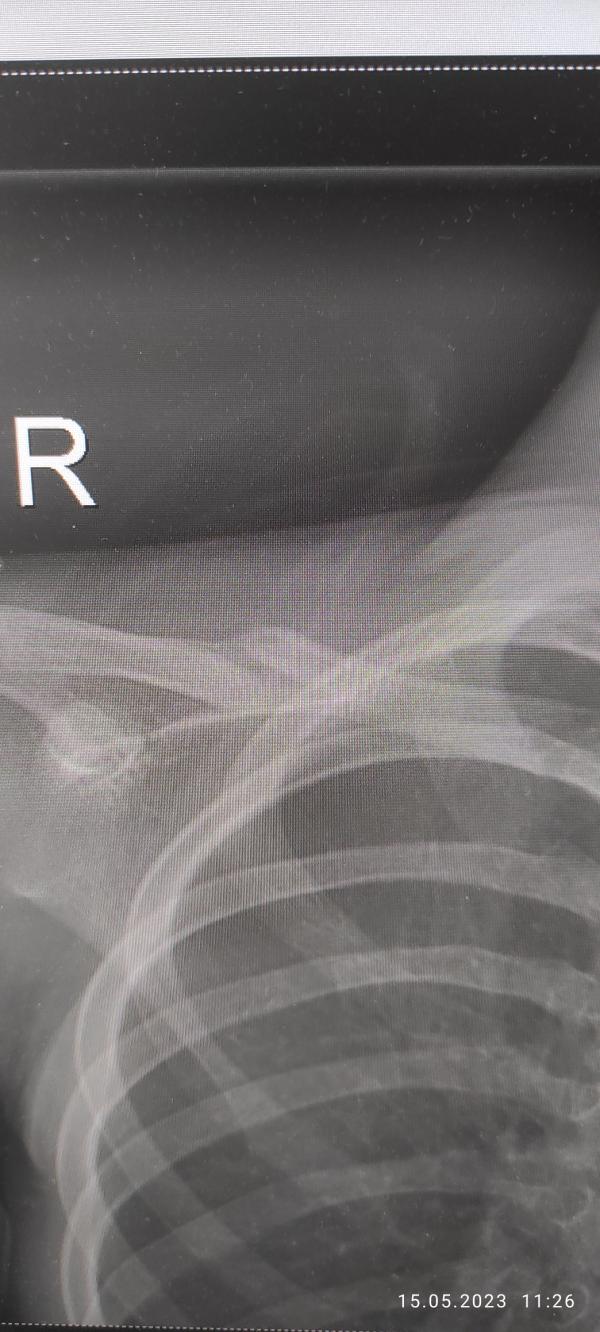

Первое фото сразу после травмы, второе - вчерашний рентген через 2,5 мес после травмы. Ключицу ломал сын на тренировке.

Мы были у травматолога в конце августа, чтобы он разрешил или запретил спорт. Сделали рентген. В итоге костная мозоль, конечно, есть. Но она достаточно крепкая, чтобы о травме забыть и заниматься любым спортом. Сейчас уже не вспоминаем никак о переломе, ничего не болит. А костная мозоль со временем уйдёт, тем более у ребёнка.